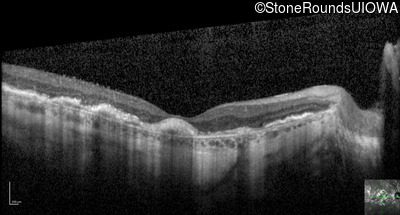

Optical Coherence Tomography - Right - 20/160 -2

Exemplar / OCT Stack

OCT Stack